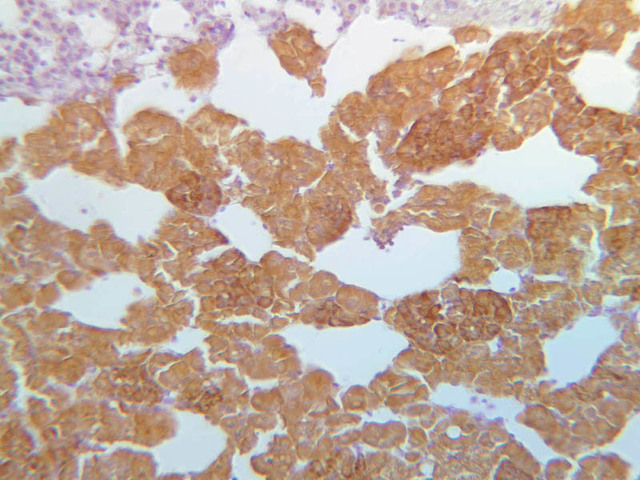

The zona glomerulosa is located immediately beneath the capsule (B-60 adrenal gland, dog [10x, 20x] [20x, 40x]; B-59 [2.5x, 10x, 20x] [2.5x, 10x, 20x]). Its constituent cells are arranged in arcs or spheres, and, owing to their relatively small size, their nuclei appear to be close together. Cells of the zona glomerulosa secrete mineralocorticoids (e.g., aldosterone). The zona fasciculata consists of parallel columns or cords of cells that radiate toward the medulla and are separated by blood sinusoids (B-60 [2.5x, 10x, 20x, 40x]; B-62 [20x, 40x]). Owing to the extraction of lipids during histological processing, the cytoplasm of cells in the zona fasciculata appears highly vacuolated or "foamy". Cells of the zona fasciculata secrete glucocorticoids (e.g., hydrocortisone & cortisone) and some gonadocorticoids (weak androgens). The zona reticularis is the deepest cortical layer and lies adjacent to the medulla (B-60 [20x, 40x]; B-62 [20x, 40x]). It is characterized by irregular, interconnecting cords of cells which are separated by anastomosing capillary networks or sinusoids. Cells of the zona reticularis, which are smaller than those of zona fasciculata and do not contain as many lipid vacuoles, secrete gonadocorticoids and some glucocorticoids.